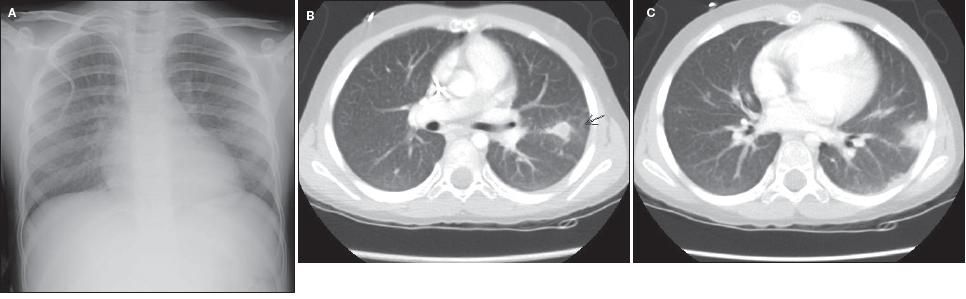

Chest radiographic findings are not sensitive for the diagnosis of invasive pulmonary aspergillosis, and radiographs have largely been replaced by chest CT scans. The most common radiographic findings are single or multiple nodules, wedge-shaped pleural-based infiltrates, and cavities (Figures 2 and 3). Diffuse infiltrates are rare.

Figure 3 – Hemoptysis developed in this patient after induction chemotherapy for acute leukemia. The chest radiograph was not revealing (A), but CT scans at 2 different cuts showed nodular infiltrates (B, C). Bronchoalveolar lavage fluid was positive for Aspergillus fumigatus and Aspergillus terreus.